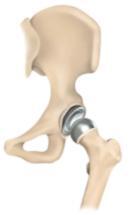

Bei der Implantation eines Hüftoberflächenersatzes werden die arthrotisch veränderten Gelenkflächen des Oberschenkelkopfes und der Hüftpfanne durch dünne Metallprothesen ersetzt. Der gesunde Knochen des Schenkelhalses bleibt dabei größtenteils erhalten. Die spezielle dafür notwendige Operationstechnik erlaubt im Gegensatz zu den "klassischen" Hüftprothesen keine Minimal invasiven Zugänge. Die Volllastaufnahme ist jedoch sofort möglich und eine schnelle Rehabilitation die Regel.

Allerdings beschränkt sich der Einsatz dieses Prothesensystems auf Patienten mit stabilen Knochenverhältnissen. Des Weiteren sollten keine ungünstigen biomechanischen Formverhältnisse vorliegen, so können Beinlängenunterschiede nicht ausgeglichen werden.